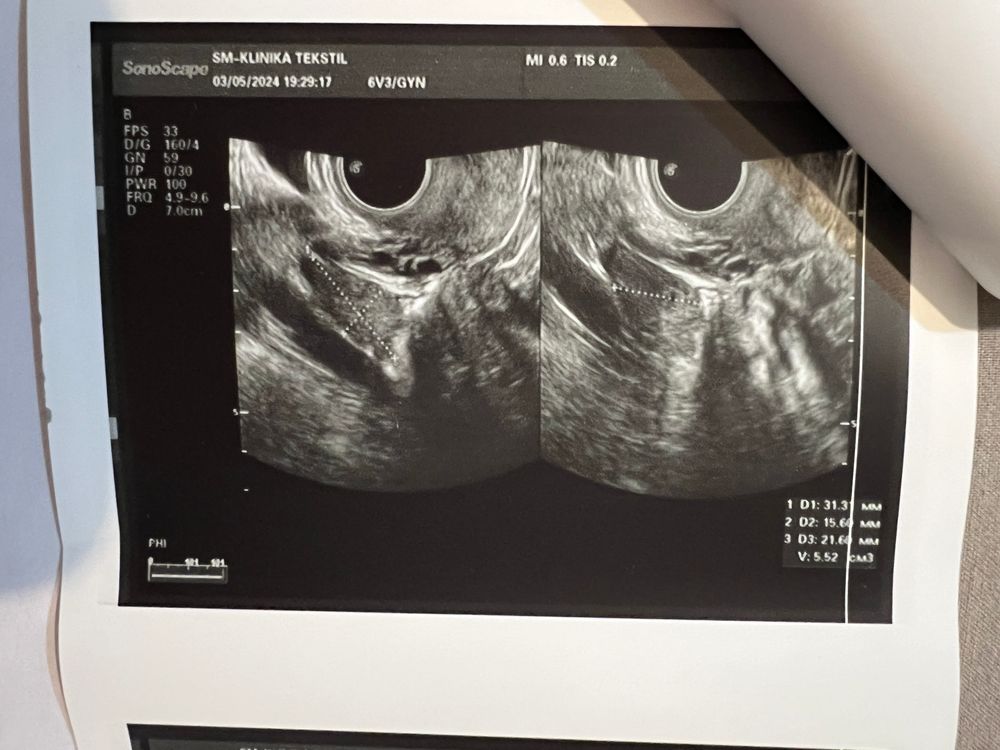

Здравствуйте! Подскажите пожалуйста 🙏Сегодня 8 дпо. УЗИ осмотр динамики лечения. Вышла с узи обрадовалась насчет жт, так как овуляций у меня почти не бывает и убежала. Но узист не указала размер 🥲и я вообще его не вижу на узи… может кто то понимает в этом? Что такое «в срезе звезчатое желтое тело». Также вела график 🙏 сейчас пью фемостон 2 фазу. ДАТА ПОСЛЕДНЕЙ МЕНСТРУАЦИИ: 27 день МЦ МАТКА расположена по центру от проводной оси малого таза, отклонена кпереди Форма: грушевидная Размеры: длина 46 мм, передне-задний размер 38 мм, ширина 52 мм. Контуры :ровные, четкие. Структура миометрия :неоднородная, по передней стенке рубец состоятельный толщиной 6 мм. М-ЭХО: 9.5 мм, соответствует фазе менструального цикла. ЭНДОМЕТРИЙ: однородный, линия смыкания не деформирована. ПРАВЫЙ ЯИЧНИК: расположен в типичном месте, контуры четкие и ровные Размеры 36х15х25 мм, объемом 7 мл Структура: в срезе 3-4фолликула, . ЛЕВЫЙ ЯИЧНИК: расположен в типичном месте, контуры четкие и ровные Размеры 31х16х22 мм, объемом 6 мл Структура: в срезе звезчатое желтое тело. ШЕЙКА МАТКИ 38х23 мм. Структура однородная ЦЕРВИКАЛЬНЫЙ КАНАЛ: не расширен, линия смыкания не деформирована ОБРАЗОВАНИЯ В ПОЛОСТИ МАЛОГО ТАЗА: нет СВОБОДНАЯ ЖИДКОСТЬ В МАЛОМ ТАЗУ: следы